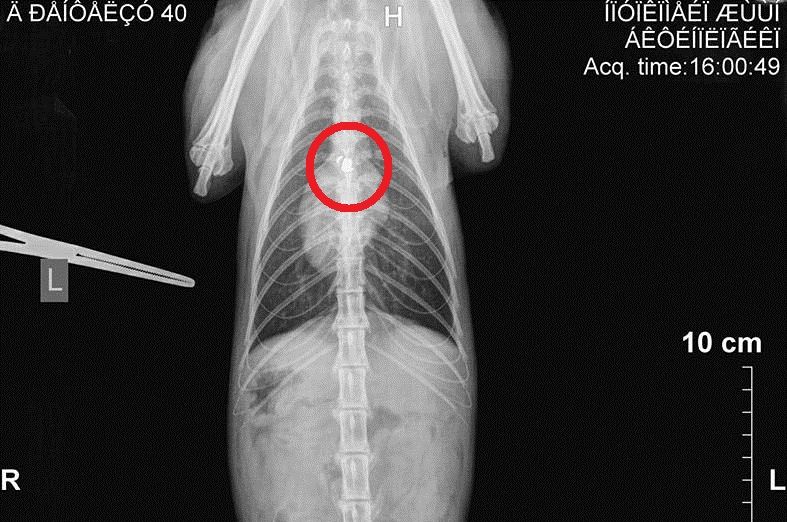

MelissiaPyrovolimeniAktinografiaΗ ακτινογραφία έδειξε σε ποιο σημείο έχει σφηνώσει το σφαιρίδιο του αεροβόλου.

Η ακτινογραφία απέδειξε ότι το σφαιρίδιο του αεροβόλου σφηνώθηκε στην σπονδυλική στήλη του ζώου με αποτέλεσμα τα πίσω άκρα του γάτου να παραλύσουν και φυσικά να χρειάζεται βοήθεια και για την ούρηση καθώς δεν μπορεί να ελέγξει ούτε αυτή τη λειτουργία του σώματος του.